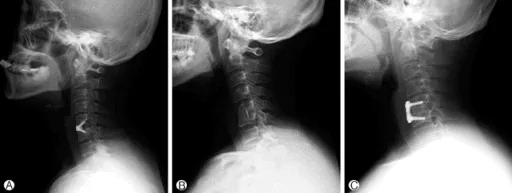

X-Ray

An X-ray provides rapid images of the bony structures of the cervical spine. It can reveal narrowed disc spaces, fractures, bone spurs, and changes consistent with osteoarthritis. X-rays do not show soft tissue structures like discs or nerves.

Traditional Fusion Surgery (ACDF)

Anterior cervical discectomy and fusion (ACDF) has been the standard surgical treatment for cervical disc herniation for decades. The procedure involves removing the damaged disc, relieving pressure on the affected nerve or spinal cord, and then permanently fusing the adjacent vertebrae using bone graft and metal hardware. While effective for many patients, fusion permanently limits the neck’s natural range of motion and transfers mechanical stress to adjacent spinal levels. Research has shown that adjacent segment disease requiring reoperation affects approximately 11% of fusion patients, and radiographic degeneration at adjacent levels develops in up to 30%.